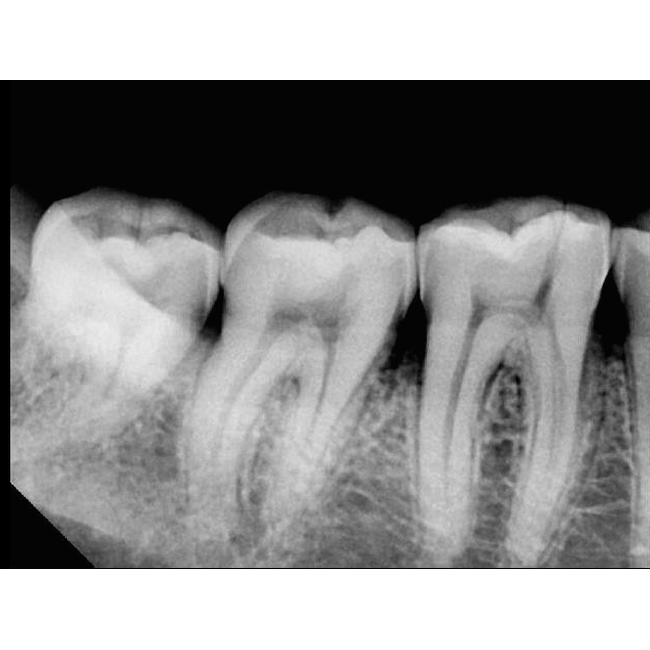

Интеллектуальная система позиционирования делает работу с EzRay Air Wall невероятно простой, а уменьшенный размер фокального пятна обеспечивает снимки высочайшего качества.

Вне зависимости от используемого датчика, EzRay Air Wall гарантирует превосходный результат благодаря фокальному пятну 0.4 мм.